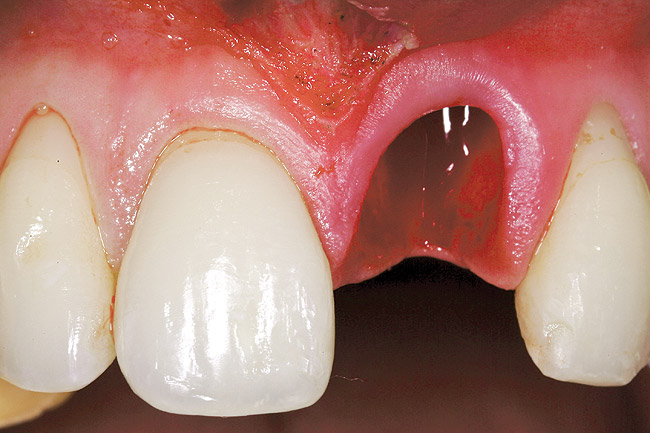

Figure 23  Case Three Atraumatic extraction, left central incisor.

Figure 23

The patient opted for the third option. After administration of an appropriate local anesthetic, a frenectomy was performed using a Nd:Yag laser. This would allow for the loosening of the facial tissues and the coronal repositioning of the pouch at the termination of the procedure. After the frenectomy, the left central incisor was removed by an atraumatic technique preserving the soft tissue emergence profile (Figure 23). Debridement of the extraction socket preceded atraumatic site preparation techniques. A 3.5-mm diameter by 13-mm tapered implant (Prima Connect, Keystone Dental, www.keystonedental.com) was placed to the appropriate depth measurements planned.38,39